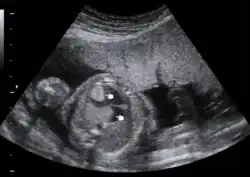

Prenatal ultrasound showing fetal cardiac rhabdomyoma

Cardiac rhabdomyomas are usually found in the ventricular walls or on the valves of the heart. With imaging techniques such as ultrasound and magnetic resonance imaging (MRI), these tumors are being detected with increased frequency and even in the prenatal period. Routine surveillance of children with tuberous sclerosis for cardiac rhabdomyoma or other cardiovascular manifestations of their disease may include electrocardiogram (EKG) and echocardiography.[12]